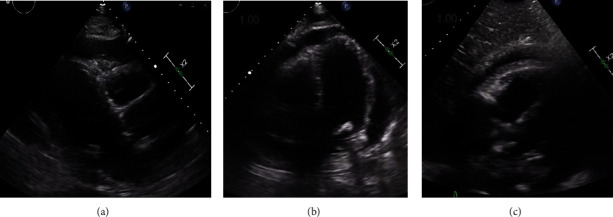

Purulent pericarditis is an extremely rare entity with only a few reported cases so far. This condition deserves prompt diagnosis because of its significant mortality rate if left untreated. A 76-year-old man with a past medical history of coronary artery disease (CAD) with percutaneous coronary intervention (PCI) to the left anterior descending artery (LAD) and right circumflex artery (RCA), ischemic cardiomyopathy with moderately reduced ejection fraction (EF 45-50%), peripheral artery disease (PAD), COVID-19 pneumonia complicated by fibrotic lung disease (on 3 liters of home oxygen), type-2 diabetes mellitus (T2DM), hypertension (HTN), hyperlipidemia (HLD), and chronic kidney disease (CKD) stage III presented with complaints of pleuritic chest pain and shortness of breath. On hospital day 1, he was afebrile and hemodynamically stable with physical exam remarkable for bibasilar crackles and dry gangrene of his right first toe. He developed progressive altered mental status, hypotension, oliguric renal failure, and respiratory distress on hospital day 6. On exam at this time, he had an elevated jugular venous distension (JVD) of 12-14 cm water, pericardial friction rub with decreased heart sounds, and orthopnea; all were consistent with cardiac tamponade clinically. An electrocardiogram (EKG) showed new ST elevations in leads I, II, and aVL with ST depression in aVR and V1 with only mild elevation in troponin I to 0.07 ng/mL. A transthoracic echocardiogram (TTE) was done on hospital day 7 and showed a moderate sized pericardial effusion with inferior vena cava (IVC) enlargement but no atrial collapse, ventricular collapse, IVC collapse, or respiratory variation in the mitral and tricuspid inflow velocities. Blood cultures grew methicillin-resistant Staphylococcus aureus (MRSA) on hospital day 6, and he was started on intravenous (IV) vancomycin. The differential diagnosis for his enlarging pericardial effusion included purulent pericarditis, uremic pericarditis, or hemorrhagic effusion. He had urgent diagnostic and therapeutic pericardiocentesis with removal of 350 milliliters of fluid. The pericardial fluid was cloudy, tan-brown with a gram stain showing gram-positive cocci in clusters and cultures growing MRSA, which confirmed the diagnosis of purulent pericarditis secondary to MRSA infection. After the pericardiocentesis, his blood pressure, respiratory distress, and renal failure improved. The source of the bacteremia was from osteomyelitis of his gangrenous, right toe with bone biopsy growing both MRSA and Streptococcus anginosus. He underwent toe amputation for definitive source control. He was discharged on hospital day 24 with a plan to complete 6 weeks of IV vancomycin.